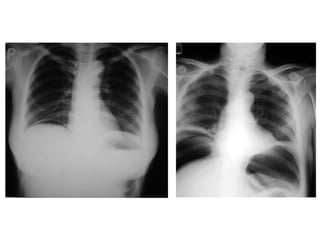

 Phim ngöïc ñöùng thaúng: tìm lieàm hôi töï do

döôùi cô hoaønh, beänh lí ñaùy phoåi..

* Daáu hieäu kinh ñieån: lieàm hôi döôùi hoaønh: xuaát hieän 6-8

giôø sau thuûng vôùi löôïng hôi khoaûng 20-50ml

Chẩn đoán phân biệt liềm hơi dưới hoành:

-Túi hơi dạ dày

-Mô phổi bình thường nằm giữa đáy phổi và cung sườn sát

trên với đáy phổi

-Hội chứng Chilaiditi